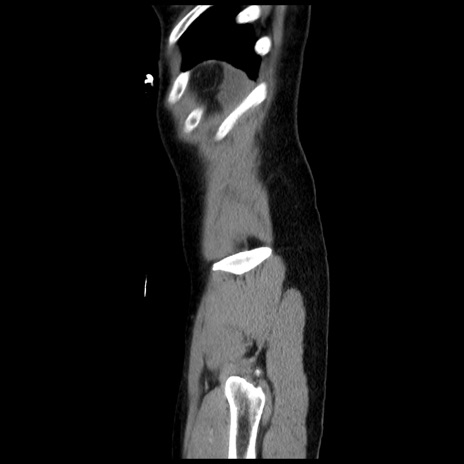

症例10(矢状断像)

【症例】 50歳代女性

【主訴】 腹痛

【現病歴】前日生レバーを食べた。今朝に排便あり。 昼前に突然発症の腹痛を生じ、当院救急外来を受診した。

【既往歴】 子宮筋腫にてで子宮全摘後

【身体所見】 意識清明、腹部:平坦、軟、下腹部やや左を中心に圧痛・反跳痛あり、筋性防御あり

【データ】WBC 7800、CRP 0.07